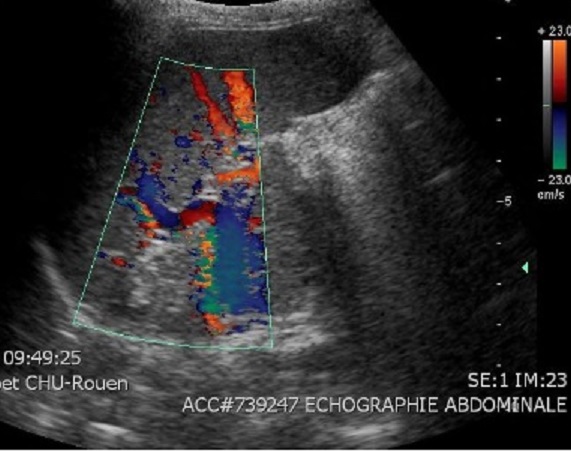

. La technique echographique de Doppler en couleur se donne

des images de artere et veine splenique en couleur et on

peut en verifie par la differenciel de sa onde : artere

splenique est triphasique et moniphasique des veines

splenique

Par la technique echographie en Doppler

on peut receceuillir image de artere et veine

splenique en couleur et peut en verifié par ;la

difference de sa pulse |

Image echograpghique de

veine splenique en bleu et en rouge de artere

splenique , la diametre de veine splenique

normalement variée entre 9 -10mm |

La forme des ondes de pulse de

artere splenique est normalement triphasique et de veine

splenique est souvent monophasique |